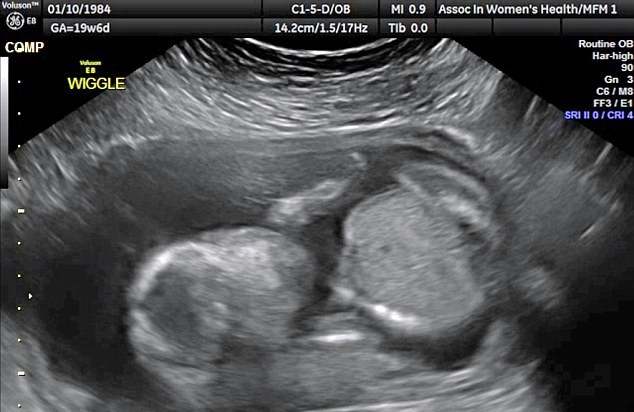

WICHITA – YOUTUBE Feto si prende a cazzotti in testa. Una coppia che vive a Wichita in Kansas è rimasta sorpresa nel vedere il feto del loro primo figlio che si prende a cazzotti in faccia. Almeno questo è quello che si vede nell’ecografia 3D pubblicata sul Daily Mail: il bambino appare molto irrequieto e sembra colpirsi con dei pugni sulla testa. Dave e Vanessa Watson sono rimasti di stucco nel vedere Edward James, questo il nome scelto per il pargolo, che si dà i pugni sul viso.

L’ecografia in questione è quella delle 20 settimane e risale allo scorso 26 gennaio. Vanessa, 32 anni , e Dave, 37, sono sposati da due anni e sono in attesa del loro primo figlio. Parlando della radiografia, Dave, un gestore di servizi per la ristorazione racconta: “E’ stato un vero choc. Stavamo guardando l’ecografia in tempo reale e improvvisamente è accaduto questo. L’infermiera si è messa a ridere e ci ha detto che non aveva mai visto niente del genere”.

“Io e Vanessa – ha continuato Dave Watson – ci abbiamo scherzato su. Mia suocera invece ha cominciato a piangere pensando che si stesse facendo del male da solo”. Vanessa nella vita lavora in ospedale e partorirà la prossima primavera.

A 20 settimane di età il feto misura, in genere, circa 26 centimetri. Il feto è già in grado di girarsi e di eseguire capriole.